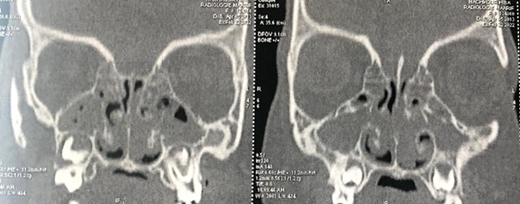

A CT scan of the nasal cavities showed a hypodense,

homogeneous, confluent process filling the maxillary sinuses, frontal sinuses,

ethmoidal cells, sphenoidal sinus and nasal cavities, in favor of bilateral

nasosinus polyposis. There is also a significant hypertrophy of the posterior

soft tissues of the cavum, leading to obstruction of the upper airway (Figures1 and 2).

Figure 2: CT scan of the nasal

cavities in coronal section, showing complete filling of the maxillary,

ethmoidal, frontal and sphenoidal sinuses and nasal cavities.